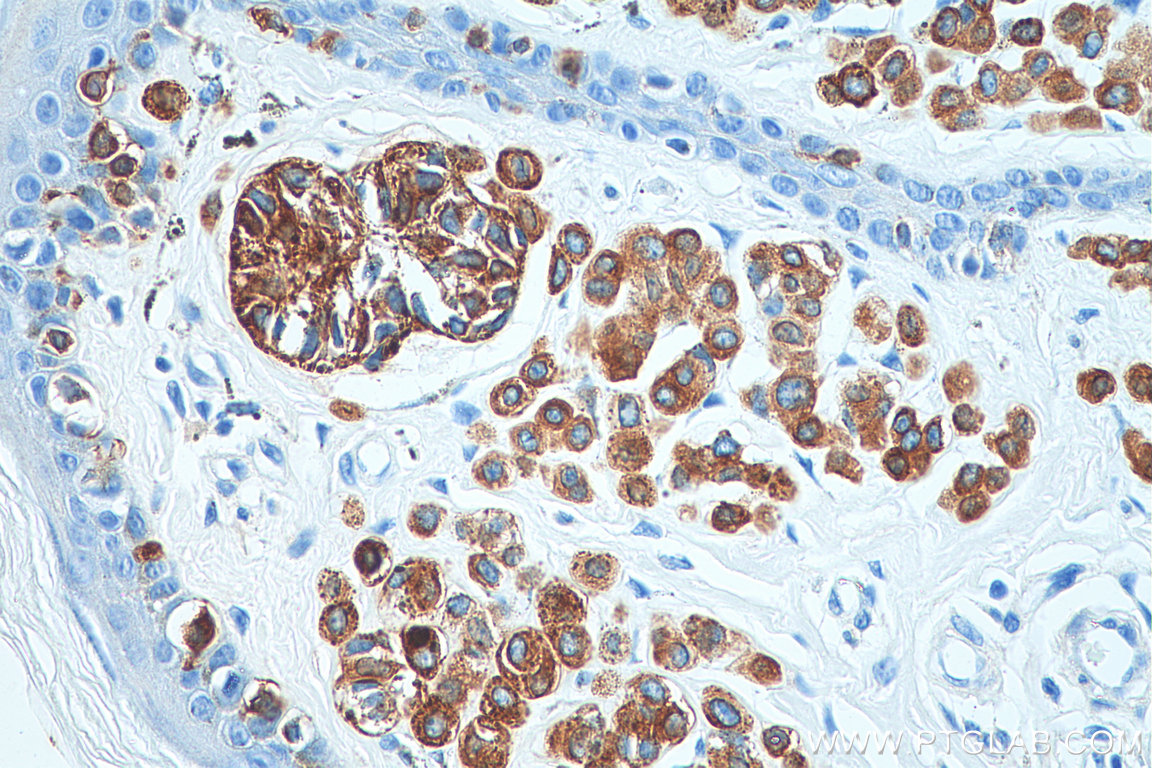

| Positive IHC detected in | human malignant melanoma tissue, human skin tissue Note: suggested antigen retrieval with TE buffer pH 9.0; (*) Alternatively, antigen retrieval may be performed with citrate buffer pH 6.0 |

Melan-A is a palmitoylated integral membrane protein of 118 amino acids with a short amino-terminal luminal domain and a longer carboxy-terminal cytoplasmic domain . The protein does not possess any detectable enzymatic activity and has not been linked to any of the numerous genetic defects that affect skin pigmentation. Melan-A is new immunohistochemical markers that can be used in the diagnosis of melanocytic lesions. (PMID: 15703212, PMID: 17445277)